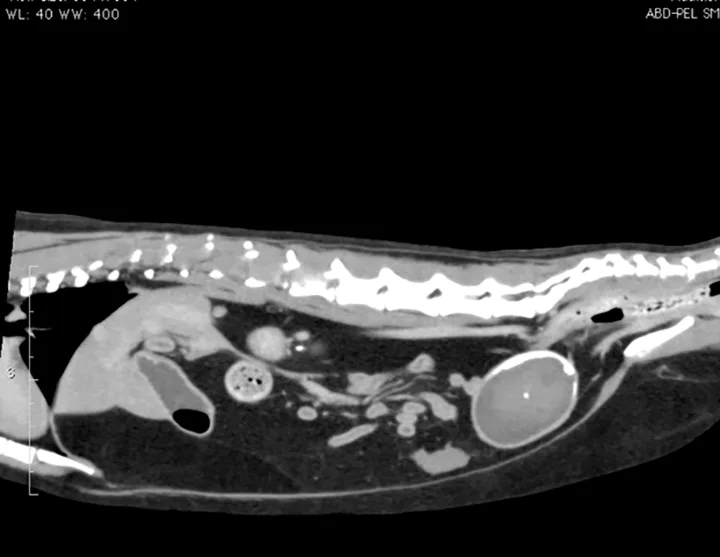

Figure 2. A large echogenic structure is present within the urinary bladder. Power Doppler image shows that there is no blood supply to this material within the urinary bladder.

Additional diagnostic tests included abdominal ultrasound (Figure 2) and computed tomography (CT) scan with IV contrast media (Figure 3).